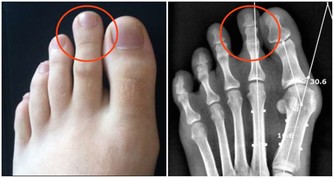

2、彎彎腳趾:消除疲憊

睡前不要進行劇烈運動,可做做“腳趾操”,用力伸直腳趾5秒後再彎曲5秒,每隻腳各做5次,有助於緩解一天的疲憊。可在泡腳時同時進行。